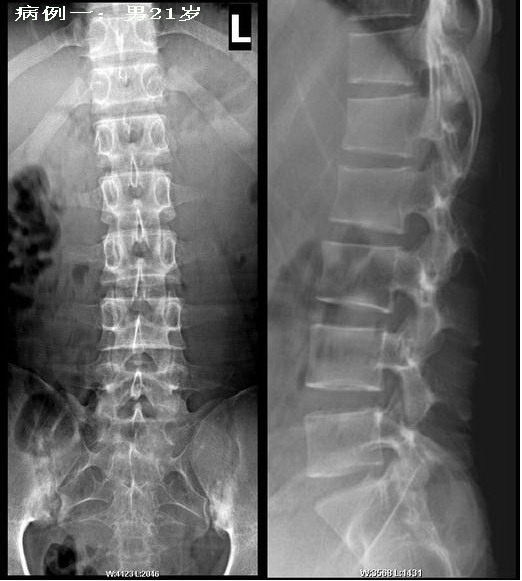

病例一:强直性脊椎炎早期病例.

男性患者,21岁,轻微腰背痛.双侧骶髂关节下缘破坏,腰椎曲度变直,骨质疏松,腰2-5椎体为方形,但尚未出现典型的竹节样改变。在北京阜外医院全面检查,诊断为强直性脊椎炎.

第2例相对较典型,但还需结合临床分析。第1例则不典型,或者说不是,其椎体并非呈方形,而是正常表现,亦没有明显骨质疏松表现。且椎小关节结构及骨质边缘亦很清楚、锐利。双侧骶髂关节下缘虽有虫蚀样破坏,但有明显硬化改变,且上中部未见明显异常。早期强直性脊柱炎也是从骶髂关节下部开始,呈虫蚀样破坏,往往伴有骨质疏松,所以边缘毛糙、模糊,一般没有明显硬化征象。而且早期累及椎小关节,亦呈类似改变。所以我不赞同早期强直性脊柱炎诊断。可考虑慢性炎症所致。建议追踪复查。

第一例是经过确诊的,注意一下双侧髋关节间隙一致性变窄,这也是强直性髋关节炎的表现.